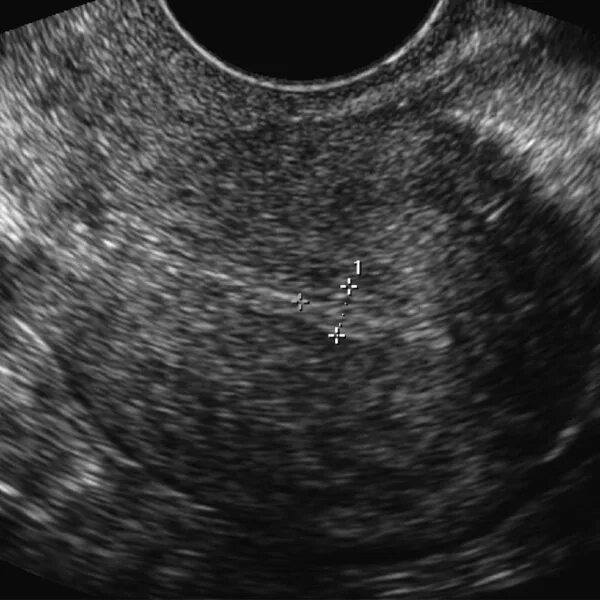

Чтобы рос эндометрий